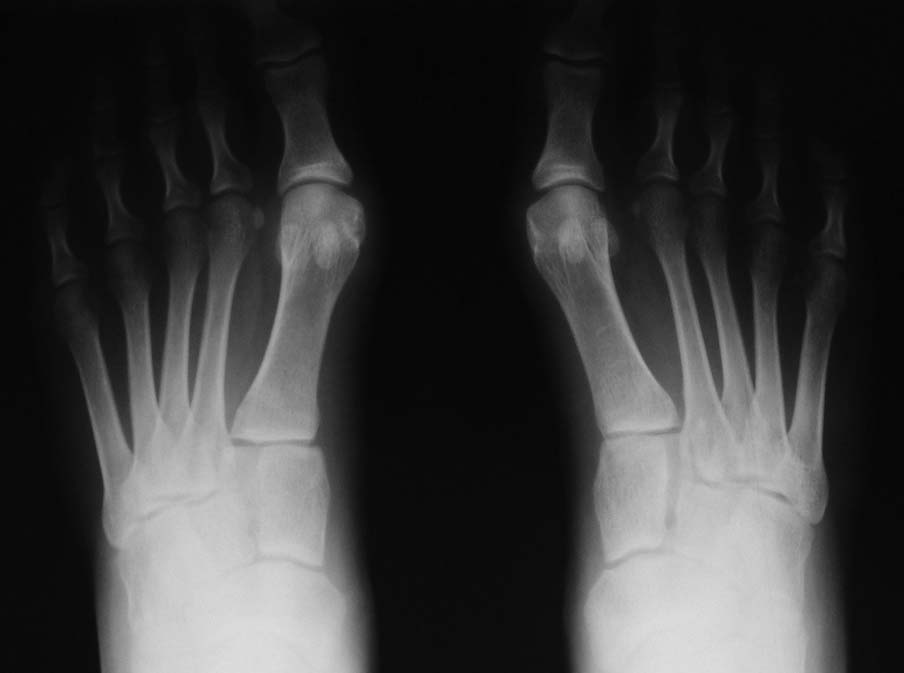

следствием просчета в планировании, а не недостатком техники. Во вложении - демонстрация

развития артроза из-за удлинения после открытой клиновидной остеотомии. Правда, это была

методика ЦИТО, но смысл тот же: дистальной остеотомии тут вовсе не было, да и спицы ни при чем.